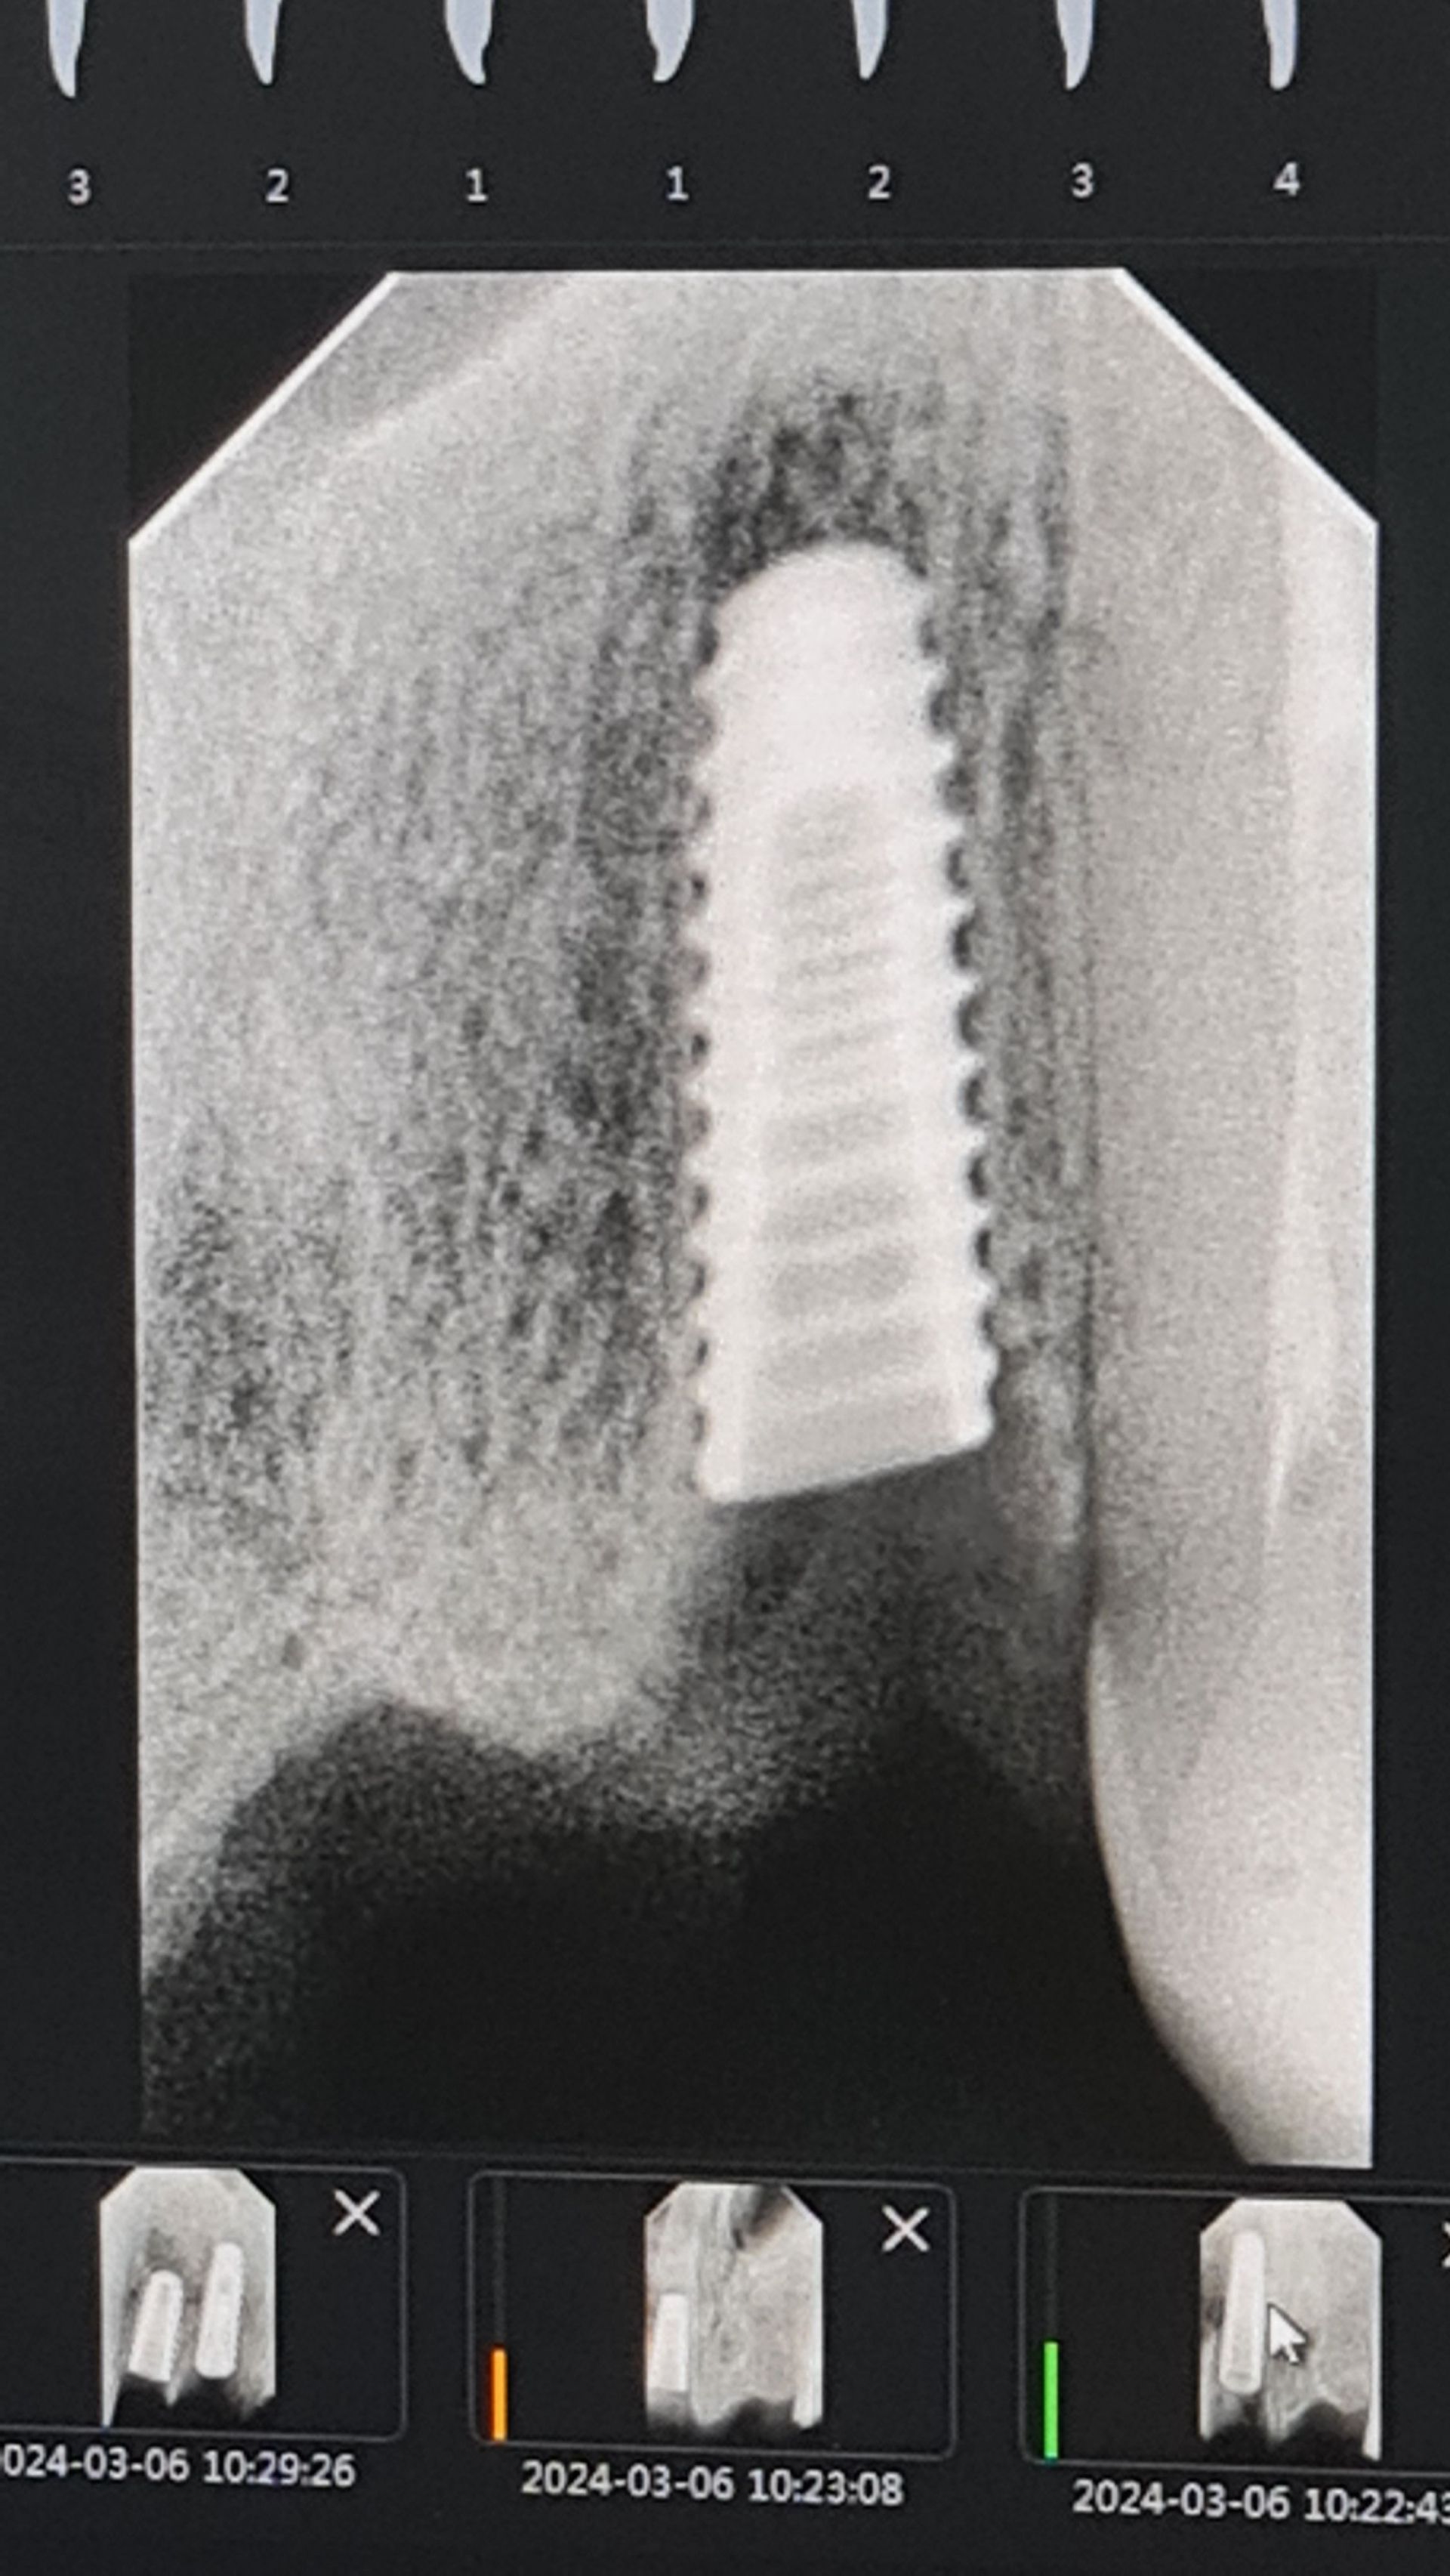

По імплантації

Імплантація - сучасний метод відновлення втрачених зубів.

Імплантат – це аналог кореня зуба, який зроблений зі сплаву металів, де у відсотковому співвідношенні переважає титан. Оскільки матеріали біосумісні з кістковими тканинами, то вони легко приживаються.

Різні виробники додають свої «фірмові» особливості кожного імплантату (наприклад, різні насічки або хімічний спосіб обробки поверхні для кращої первинної стабілізації і подальшого приживлення)

Також деякі виробники дають довічну гарантію на свої імпланти